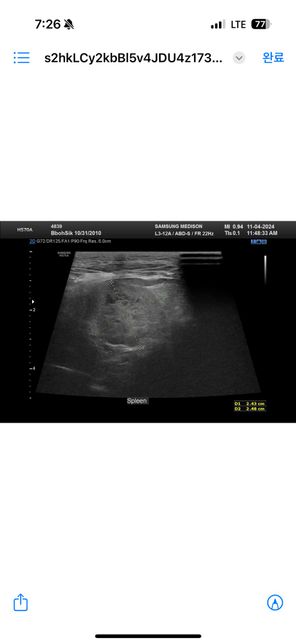

- 반려동물 건강반려동물Q. 강아지 건강검진 복부초음파에 관해서 질문드려요ㅜㅜ안녕하세요 최근 두군데에서 16살 노령견 복부초음파를 찍었습니다 그런데 두군데에서 서로 다른결과를 말씀하셔서요 한군데는 비장종괴 2.5cm 라고 하시고 한군데에서는 안커지는거보니 비장종괴가 아니라 부신종양이라고 말씀하시던데 뭐가 맞는지 모르겠어서요ㅠ 전에 초음파 찍은게 잇엇던거 같은데 사진 둘중에 뭔지는 잘 모르겟지만 혹시나 아시면 알려주실수있으실까요ㅜㅜ